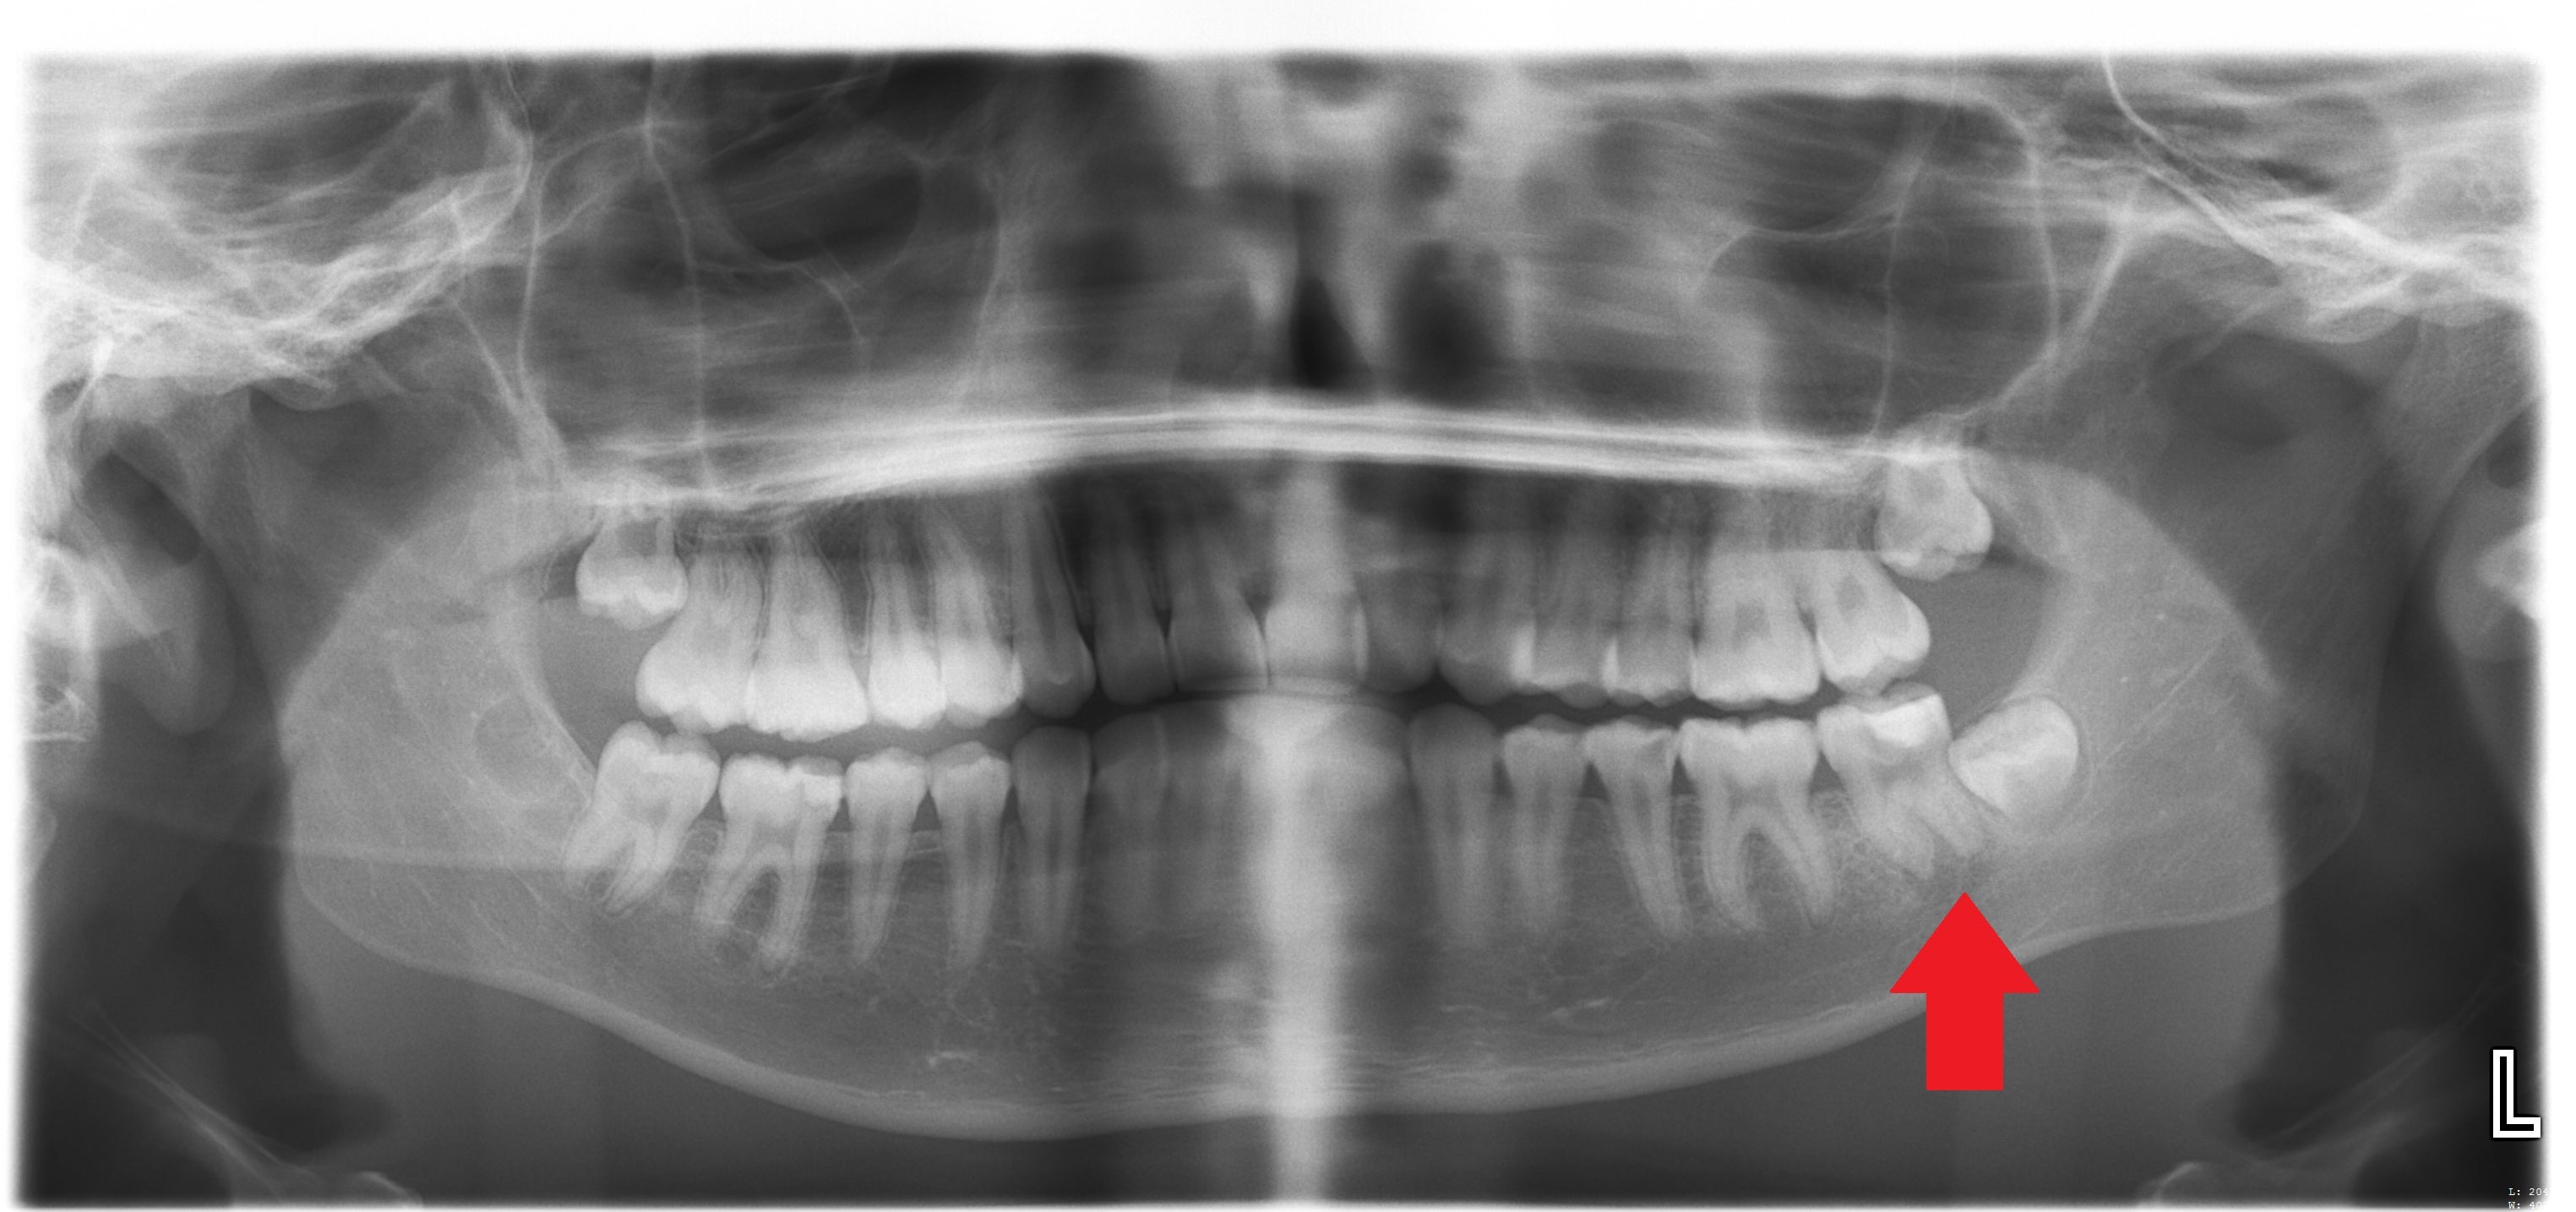

A check-up revealed one of her teeth on the left-hand side, LL7, had cracked, and she said a dentist, who cannot be named for legal reasons, cleaned it and placed a sealant on it.

She said it was revealed that the cracked tooth and abscess were a result of untreated decay, and she was told the abscess was on the verge of bursting and causing sepsis.

After being put in touch with the Dental Law Partnership, which completed further investigations and analysis, it was revealed Katelyn’s dentists failed to diagnose and treat decay for years.

The progression of the decay resulted in the infected abscess, the emergency hospital admission and the need for an operation and tooth removal, all of which “could have been easily avoided”.